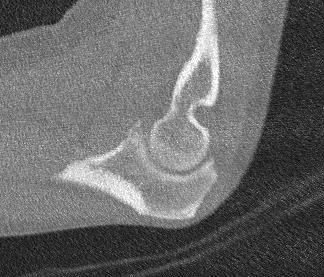

Regan and Morrey classification of transverse coronoid fractures

Elbow stability related to size of coronoid fragment

| Type I | Type II | Type II |

|---|---|---|

| Small coronoid process fracture | 50% of coronoid process | > 50% coronoid process |

| Usually stable |

Capsular attachment Elbow unstable |

Capsule + MCL attachment Elbow unstable

|